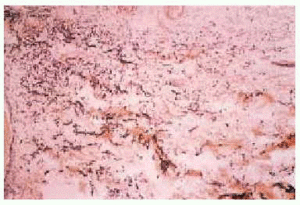

Mujer de 18 años que desde el nacimiento presentó lesiones de piel. En el examen físico se observó en la región submamaria y parte lateral de tórax derecho unas 20 lesiones papulosas, ovaladas, aisladas, de 4 a 6 mm de diámetro, de color de piel normal, de superficie lisa y asintomáticas. Su distribución era zoniforme, terminando en la línea media anterior del abdomen y extendiéndose hacia la zona posterolateral del tórax sin llegar a la columna vertebral (fig. 1). A la palpación la consistencia era blanda, con la sensación de herniación. De aparición connatal, habían permanecido estables hasta el momento de la consulta. Resto de la piel sin lesiones. El estudio oftalmológico, óseo, neurológico, cardiovascular y endocrino no mostraron anormalidades. Antecedentes personales y familiares sin particularidades. Los análisis de laboratorio fueron normales. Se realizó una biopsia en el límite entre piel sana y enferma. Se efectuaron las técnicas de hematoxilina-eosina (HE), ácido periódico (PAS) y técnica de fucsina-aldehído de Gomory para fibras elásticas. En la histopatología se apreciaron dos áreas diferentes. En la zona clínicamente normal la dermis superficial mostró la presencia de fibras elásticas oxitalámicas y elaúnicas normales, y en zona patológica se observó ausencia casi total de las mismas con franca fragmentación (fig. 2). Las fibras elásticas de la dermis reticular profunda eran normales.

Fig. 2.--En esta figura se observan dos áreas diferentes: presencia de abundantes fibras elásticas en la mitad izquierda y franca disminución, con elastorrexis, en la parte derecha.